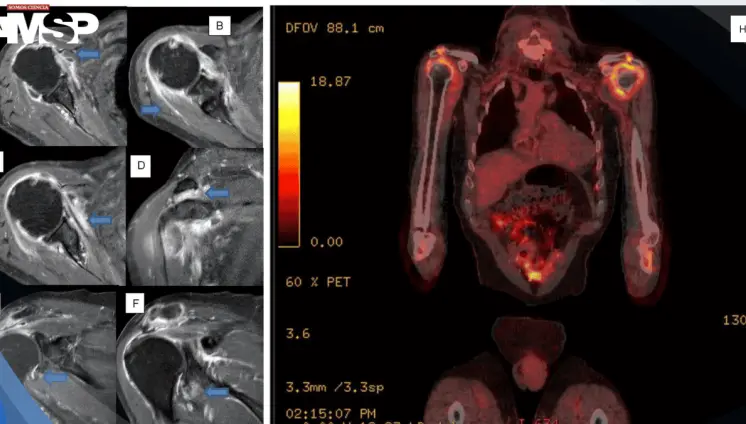

Dolor persistente en hombros y rigidez matutina revelan un caso severo de polimialgia reumática